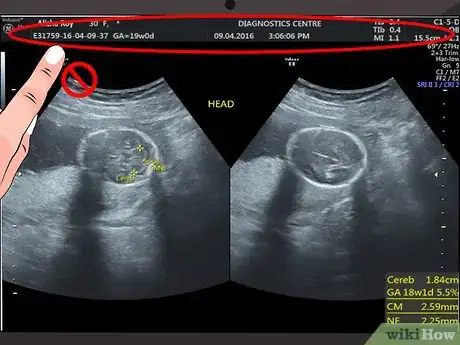

1Disregard the text and numbers at the top of your scan. Most hospitals and ultrasound centers use this space to include details like your name, hospital reference number, or ultrasound machine settings. Since this information does not have anything to do with what you see on the ultrasound image, you can ignore this information.[1]

2Start from the top of the image. The top of the screen or printed image is where the ultrasound probe was placed. In other words, the image you see shows what the organ or tissues look like from the side rather than from the top.[2]

- For example, if you are having an ultrasound of your uterus, then what you see at the top of the screen or printed ultrasound would be the outline of the tissues above your uterus. As you look further down the screen, you will see deeper tissues, such as the lining of your uterus, the inside of your uterus, and the back of your uterus.

1Identify your womb. You can identify the outline of your uterus by finding the white or light grey line around the edges of the ultrasound image. Just inside of this area, there should be a black area. This is the amniotic fluid.[6] [7]

2Spot the baby. Your baby will also look grey or whitish and will be located within the amniotic fluid (the dark area inside of the womb). Look at the area within your amniotic fluid to try to make out the outline and features of your baby.

- The details that you see in the image will depend on the stage of your pregnancy. For example, at eight weeks, the fetus will look something like a gummy bear or a baked bean; at 12 weeks, you may only be able to identify the head of your baby; while at 20 weeks, you may be able to see the spine, eyes, feet, and heart.[8]